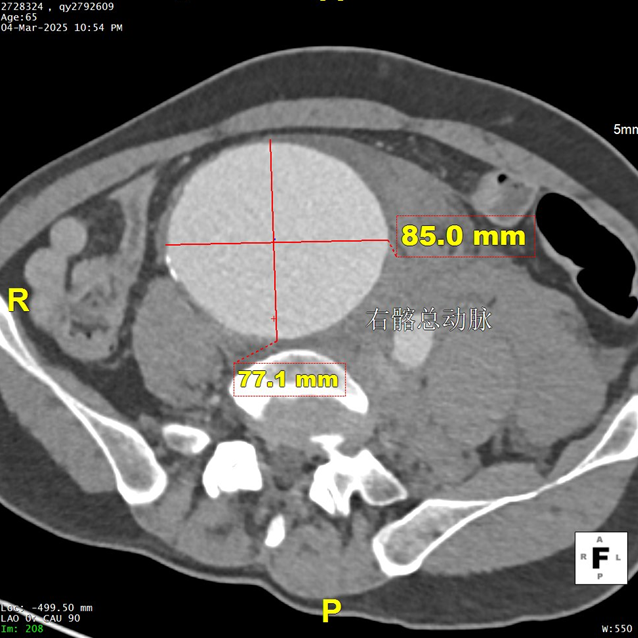

现病史:患者7小时前无明显诱因出现腹部胀痛不适,以下腹部为主,无发热、恶心、呕吐,无头晕、头痛等特殊不适,因症状持续不缓解,遂来我院急诊就诊,行腹主动脉(下腹部、盆腔段)CTA示:腹主动脉下段,右侧髂总动脉动脉瘤形成,右侧巨大髂总动脉(直径85.0mm*77.1mm)有明显造影剂溢出提示破裂,腹主动脉周围、左侧肾周、左侧腰大肌前缘及骶前积血较前明显增多,于急诊抢救室出现一过性意识丧失、血压下降休克状态,予积极补液后症状好转,现为进一步治疗,急诊以“腹主动夹层动脉瘤;髂动脉巨大动脉瘤破裂”收入院。

二、术前CTA详解